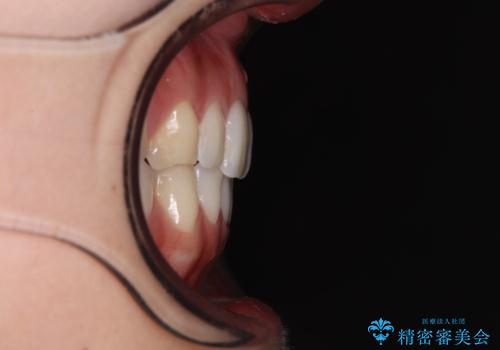

前歯の重なりをインビザライン・モデレートで矯正治療

- 上下前歯の重なりを気にして来院された患者様です。

安価なインビザラインパッケージを用いての治療を希望されており、デコボコの程度が中等度であったため、インビザライン・モデレートを用いて矯正治療を行うこととしました。